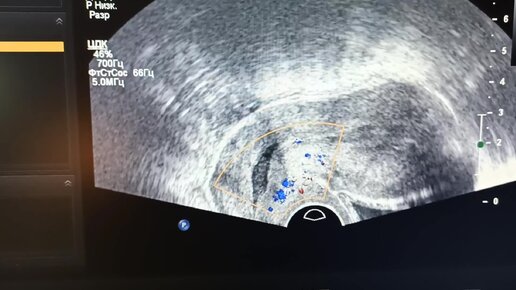

УЗИ для начинающих врачей: полип эндоцервикса.